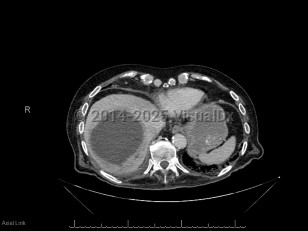

Pyogenic liver abscess

A pyogenic liver abscess is a collection of pus in the liver as the result of bacterial (or rarely fungal) infection.

The symptoms of pyogenic liver abscess are nonspecific. The two most common symptoms are fever and abdominal pain. In one review, patients had symptoms for a median of 14 days (range 1-90 days) prior to hospital admission. Some patients will have associated nausea, night sweats, and weight loss. A minority of patients have jaundice. Laboratory evaluation will usually reveal abnormal liver enzymes and an elevated white blood cell count.